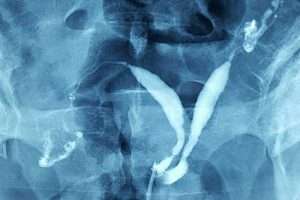

İki Taraflı Salpenjitis Istmica Nodosa (SIN) ve Hidrosalpinks

Tüplerde Sıvı Birikmesi